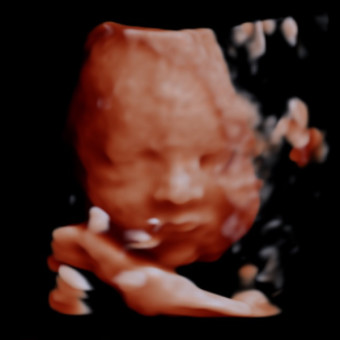

Baby E’s Arrival

December 22, 2025